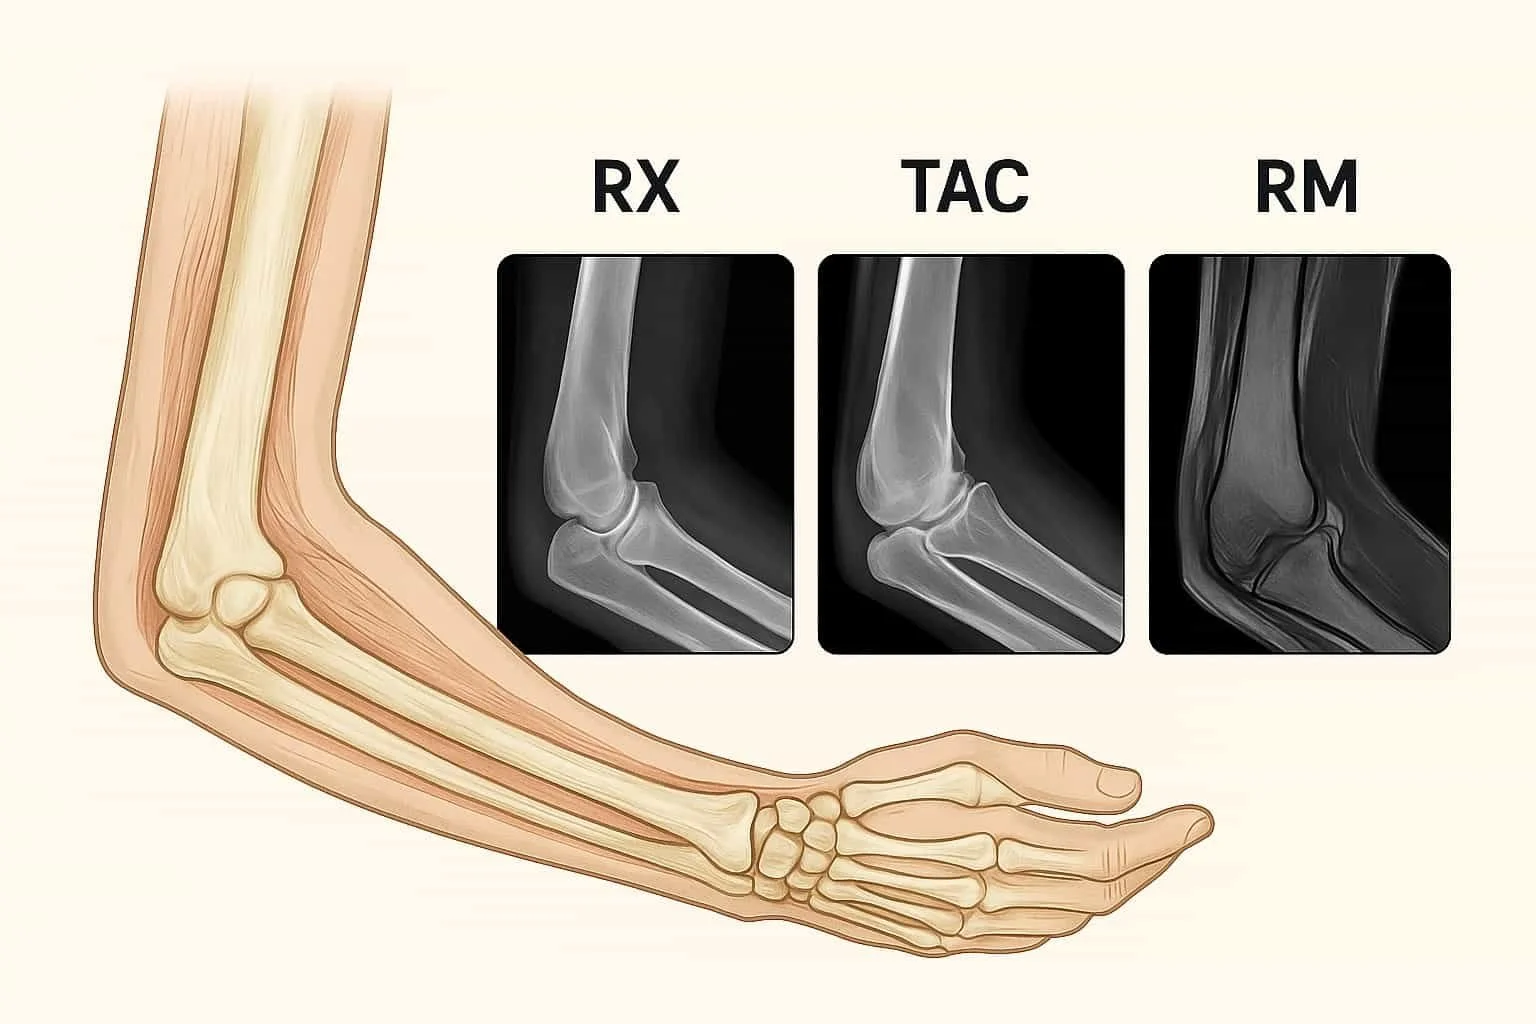

Na área da saúde, os exames de imagem são ferramentas fundamentais para o diagnóstico médico. No entanto, é comum que os pacientes tenham dúvidas sobre as diferenças entre os principais métodos: Raios X, TAC (Tomografia Axial Computorizada) e Ressonância Magnética.

Embora todos permitam "ver por dentro do corpo", utilizam tecnologias diferentes e são indicados para situações distintas.

O exame de Raios X utiliza radiação ionizante (raios X) para produzir imagens bidimensionais do interior do corpo. Os tecidos densos, como os ossos, absorvem mais radiação e aparecem mais brancos, enquanto tecidos moles aparecem em tons de cinzento.

A TAC é um equipamento que também utiliza radiação ionizante. No entanto, em vez de uma única imagem plana, como ocorre no Raios-X, o aparelho roda à volta do corpo, captando múltiplas imagens que são depois processadas por computador para gerar imagens detalhadas em cortes (fatias) do corpo.

A Ressonância utiliza campos magnéticos e ondas de rádio, sem radiação ionizante. O aparelho capta a resposta dos tecidos corporais a esses estímulos, gerando imagens de alta definição, especialmente de tecidos moles.